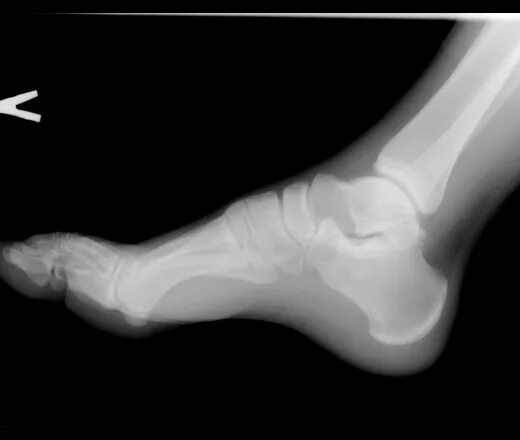

Болезнь шинца у детей код по мкб